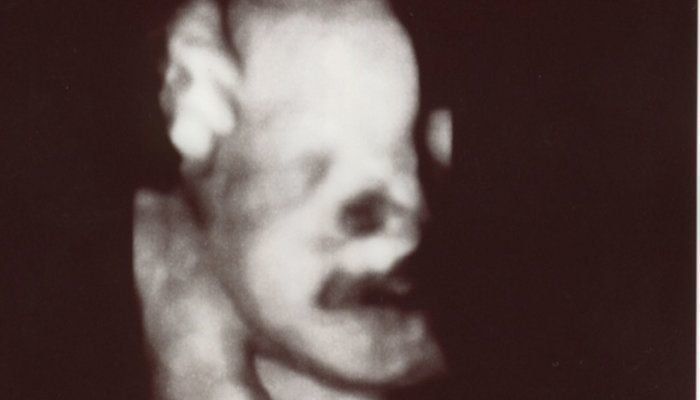

はやしなおさんの妊娠34週目のエコー写真 妊婦生活いよいよラストスパート!

どうやらおなかの赤ちゃんには、すでに髪の毛がしっかり生えているようで、眉毛もうっすら写っています。頭の髪の毛は黒々して、もう伸びているようにも見えます。頬の肉付きもだいぶ良くなり、顔全体がふっくらしています。この時点で推定体重は2500gを超えており、「少し大きい子だね」と言われていました。長女が2600g代で産まれてきているので、すでに近いサイズの赤ちゃんがおなかにいるのかと思うと、いよいよだと少し緊張しました。

エコー中も手を顔の近くでよく動かしており、顔の一部が手で隠れて黒くなっています。口も少し開いているようです。